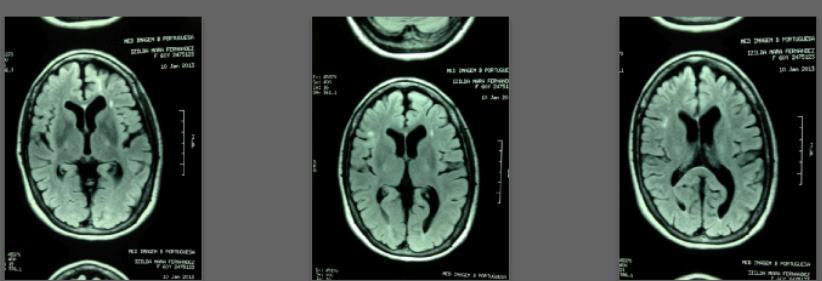

Appears that Vitamin D can induce remission in recent Multiple Sclerosis Less hyperintense areas on MRI after LOTS of vitamin D

Before = 2008

Starting daily dose 25,000 IU; increased in stages to 80,000 IU on October 28, 2010. Asymptomatic since 2010.

After = 2013